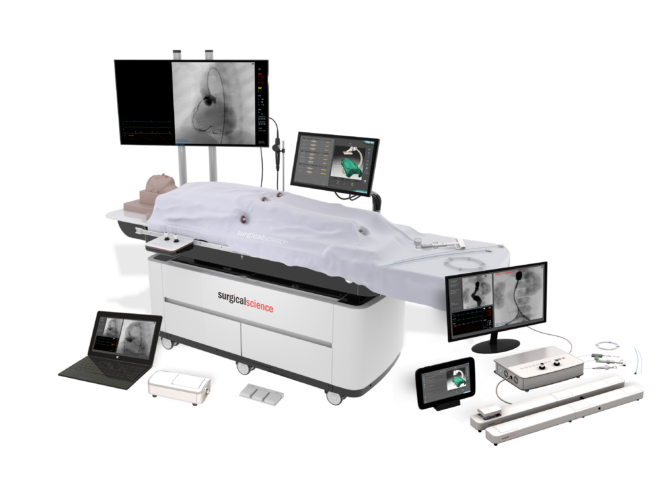

The ANGIO Mentor simulator is an essential tool for clinicians to practice and acquire the skills needed for performing endovascular interventions. Trusted by medical associations, hospitals, training centers, and the medical device industry globally, it provides trainees with realistic clinical settings to practice endovascular interventions using fluoroscopic and ultrasound guidance.

Offers true-to-life simulation of the clinical environment, including advanced imaging modalities like fluoroscopy/echocardiography, hemodynamic monitoring, medications, and interventional devices

- Available in various platforms to fit any need, from stationary, human-sized manikin to ultra-portable platforms